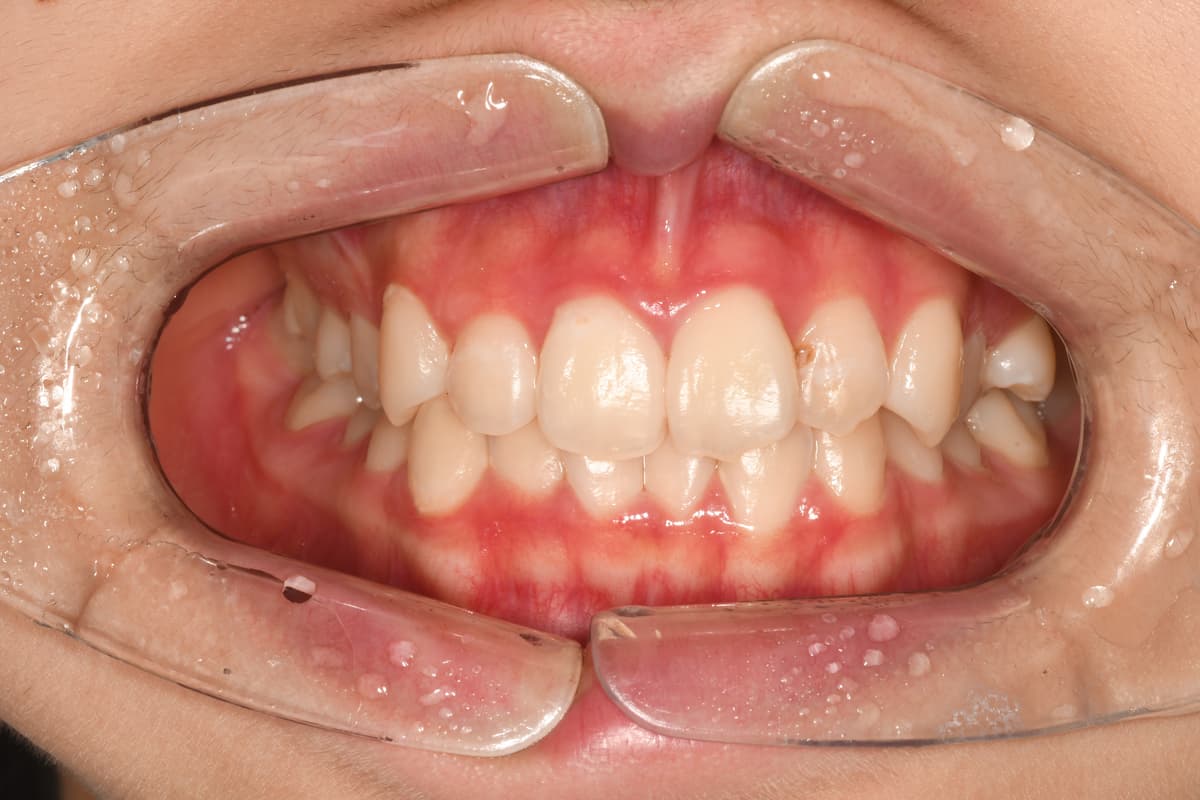

교정 치료 전후 사례

교정과 전문의가 직접 진료한

실제 환자 케이스입니다

김●● · 일반 교정

After